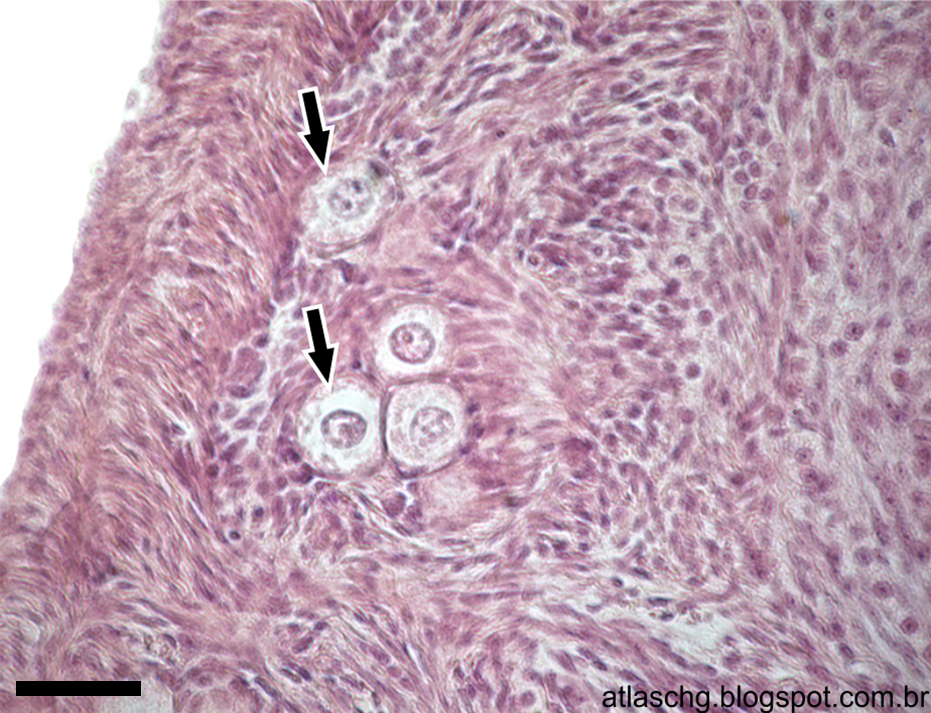

Corte de ovário. Folículo primário multilaminar em detalhe. Coloração: Hematoxilina e Eosina (HE). Barra = 40µm.